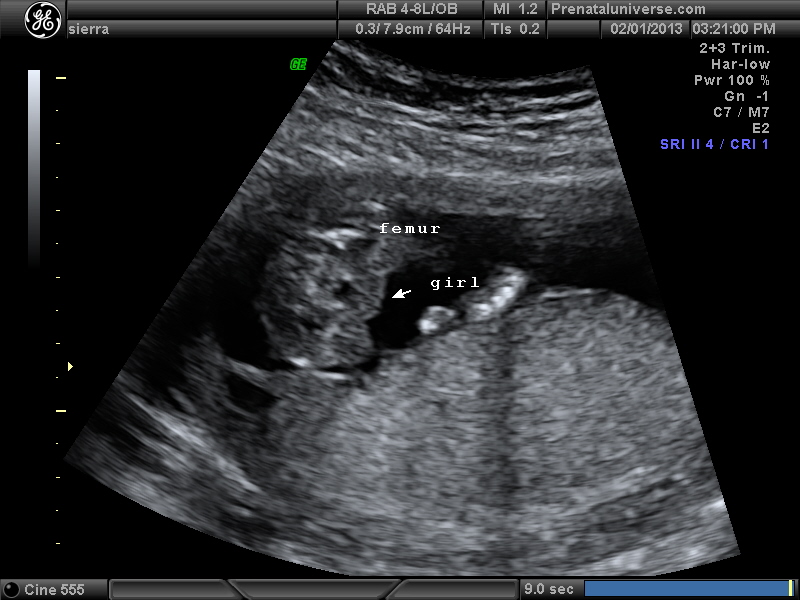

UPDATE!!!! Tech says girl. I was 16 w 1 day. Everyone agree? Nub shots were no help. Hoping this potty shot is more clear. In the video there were times it looked like there was something between legs but every still shot looks Girly I thinkTy everyone

I'm curious about the area behind the black spot. I believe he said black spot is babys bladder. the area the arrow is pointing to looks girly but the area behind the black spot looks different??? thanks all

UPDATE!!!!!16 weeks new pics! girl!? please take a look!